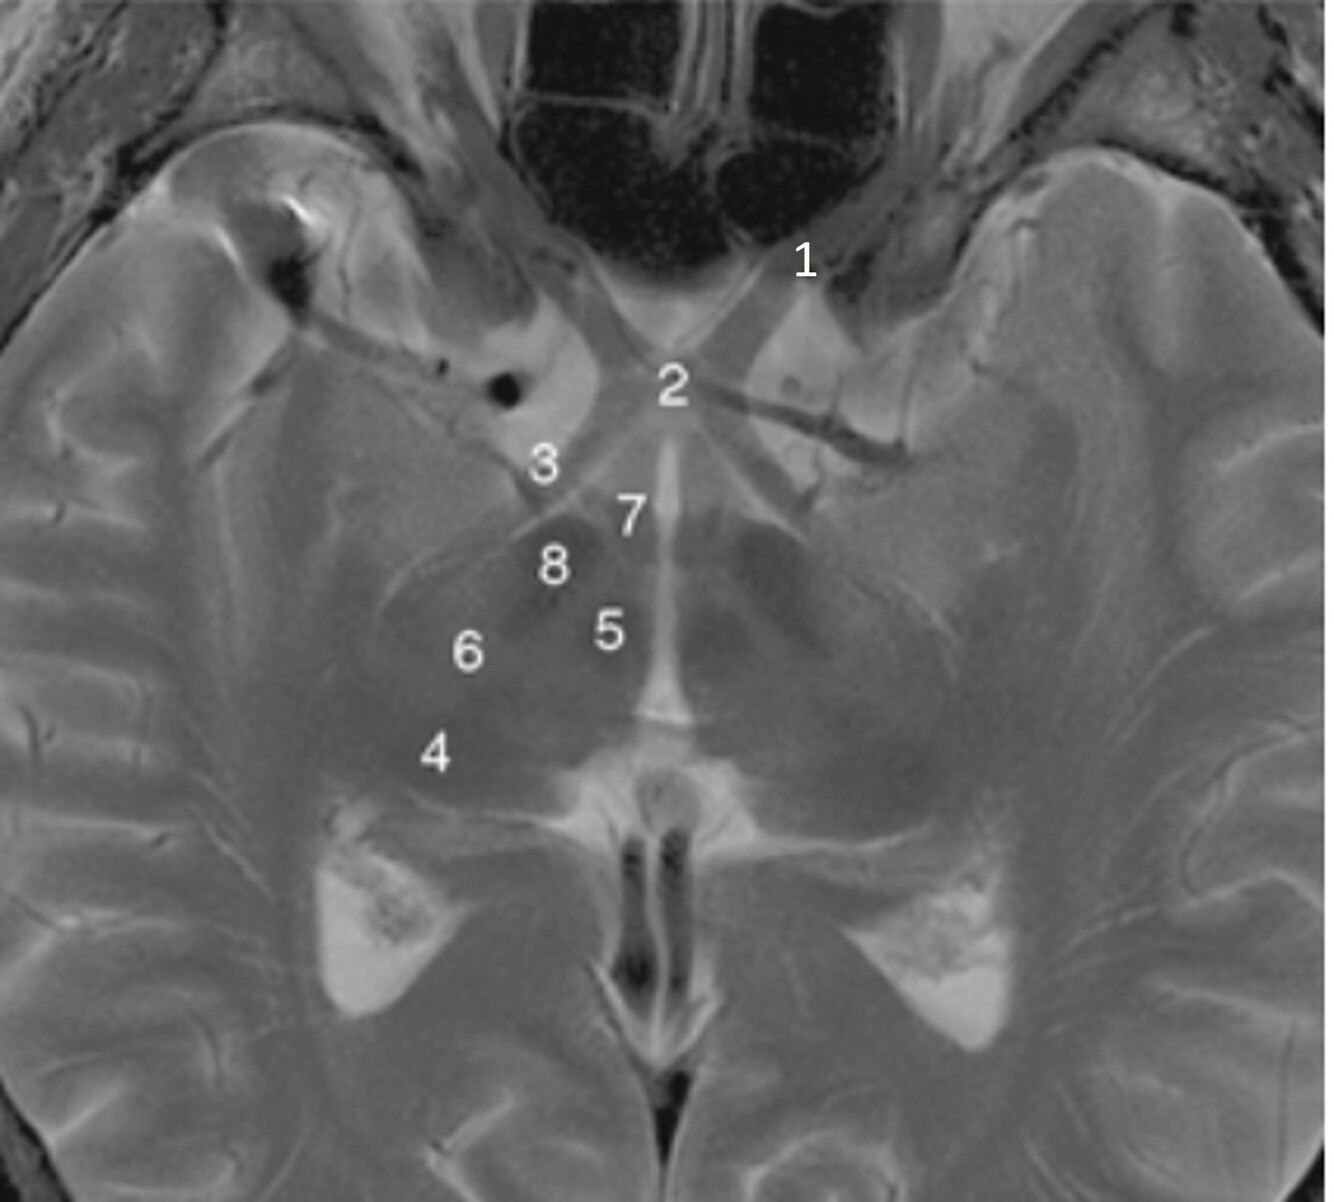

Label 2,3,4,5,7,8

2=Rt Caudate nucleus

3=Corpus callosum

4=Lt lateral ventricle

5=Third ventricle

7= Septum Pellucidum

8= Rt Interventricular foramen